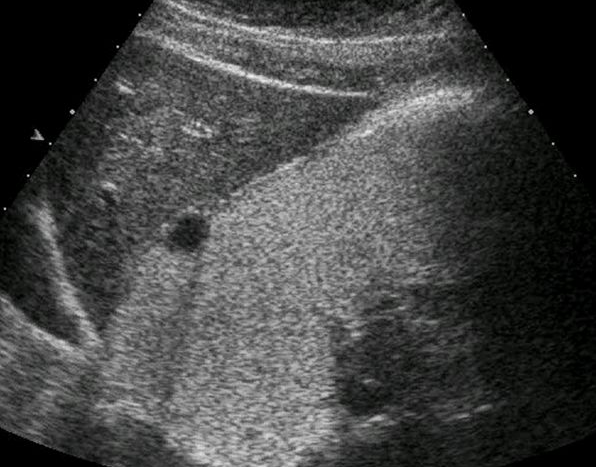

十二指肠球壁溃疡

胃造影用的是什么机子超声诊断科新技术|胃肠超声造影检查,让您舒舒服服做完肠胃筛查!_https://www.jmylbn.com_新闻资讯_第9张